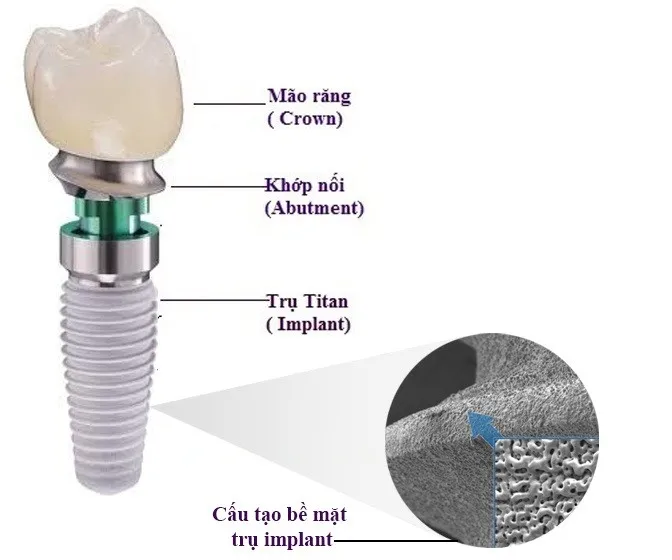

Cấy trụ răng là một trong những kỹ thuật nha khoa hiện đại giúp phục hồi răng đã mất một cách hiệu quả, đảm bảo cả về

Trong thời đại hiện nay, nhu cầu phục hồi răng mất ngày càng tăng cao, đặc biệt với phương pháp cấy ghép implant. Việc hiểu rõ về